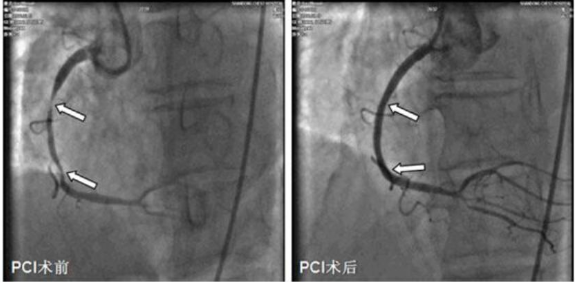

c.造影显示血管病变。如果造影显示血管狭窄到一定程度,医生会建议您做球囊扩张或支架植入术。

d.扩充球囊使冠状动脉管腔增大,血流改善。

e.支架植入血管后,扩张直至撑开血管腔。

回撤器械,支架将永远留在病变血管内,以保证血管通畅,增加血供。